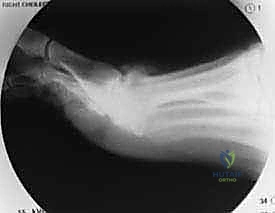

- التصوير بالأشعة السينية (X-rays): تُجرى الأشعة في وضعية الوقوف (تحميل الوزن) لرؤية المفصل في حالته الوظيفية. تظهر الأشعة بوضوح حجم النتوءات العظمية، ومدى تضيق المساحة المفصلية نتيجة تآكل الغضروف.

تُعد جراحة "استئصال النتوء العظمي الظهري" الإجراء الجراحي الأكثر شيوعاً ونجاحاً لعلاج تصلب إبهام القدم في مراحله المتوسطة (الدرجة 1 و 2، وبعض حالات الدرجة 3). كلمة "Cheilectomy" مشتقة من اليونانية، وتعني "إزالة الشفة"، في إشارة إلى إزالة الحافة أو النتوء العظمي الزائد.

- استئصال النتوء العظمي: باستخدام أدوات جراحية دقيقة جداً (مثل المنشار الجراحي الدقيق أو الأزاميل الخاصة)، يقوم الدكتور هطيف بإزالة النتوء العظمي الظهري. يتم عادةً إزالة حوالي 25% إلى 30% من الجزء العلوي للعظمة المشطية الأولى.